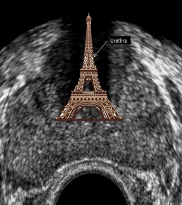

What is the Eiffel tower sign?

Shadowing created by dense tissues in area of urethra and verumontanum

Identify this image.

Peripheral zone

Central and transitional zone

Urethra